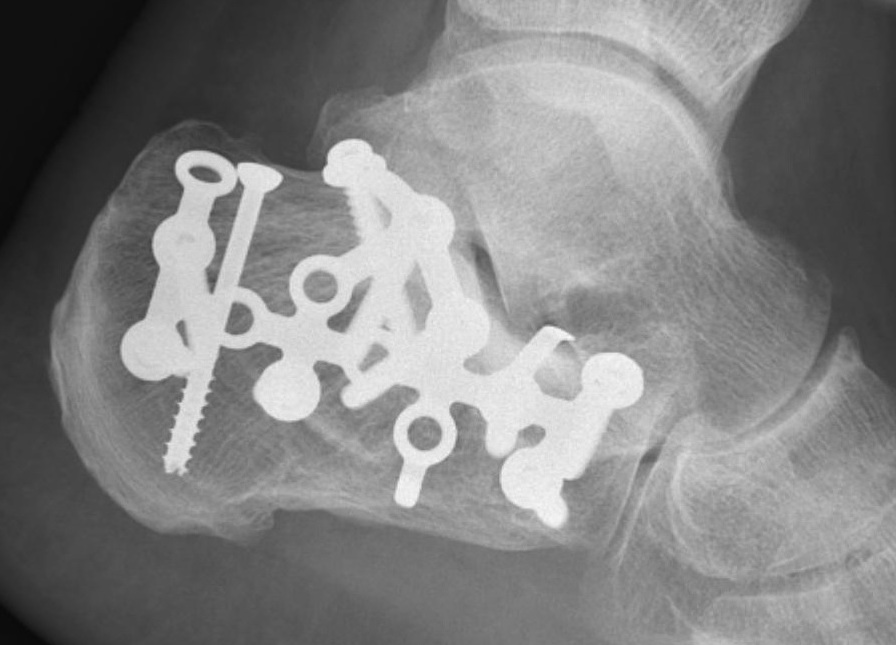

Minimally invasive surgery via sinus tarsi approach

Arthrex MIS calcaneal plating system

Acumed MIS calcaneal plating system

Use lateral plate with minimally invasive techniques